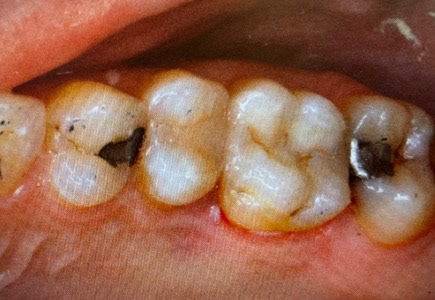

16 Pre-op